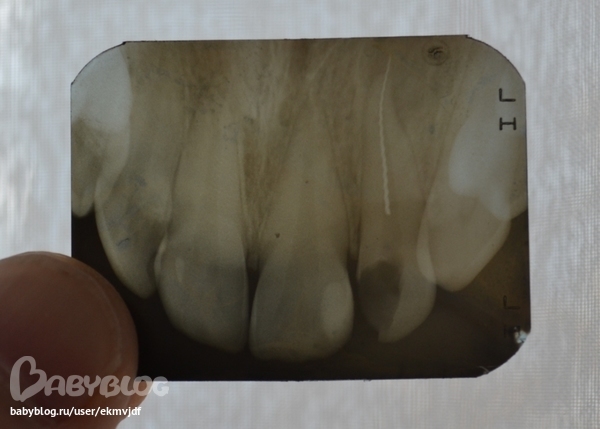

Для начала он меня отругал за рентген,сказал что во время беременности нельзя делать. На снимке видно,что у меня в зубе обломок инструмента, причем довольно большой. Хотели удалять зуб, но жалко стало, решили побороться за него. Доктор пытался вытащить обломок, не поглучилось. Положил мета пасту и сказал приходить через 20 дней. Пришла, а у него машинка сломалась, да и оказалось, что он не ставит световые пломбы, а обычная заметна будет. Пошла в часную стоматологию, там стоматолог был очень удивлен моему обломку, сказал что никогда таких не видел, и загнул цену, которая мне не покарману. В итоге я нашла другого стоматолога, она конечно тоже удивилась, глядя на мой снимок, но зуб залечила, за гораздо меньшую цену. Это было три дня назад, у меня семь месяцев беременности. К вечеру зуб немного болел (нервы удалены), он как бы не мой был,как чужой, я не обратила внимание. На утро болел уже не зуб, а опять половина носа, около крыла носа образовалась шишечка, она и болит. Пошла вновь к стоматологу (к той, которая залечила). Она развела руками,мол я не виновата, надо было тогда удалять, а я сама пришла лечить.Да я ее и не виню, мне главное чтобы она помогла..... Она сказала,сто тот снимок уже не актуален, а новый делать нельзя (из-за беременности). Сказала подождать, может пройдет. Уже третий день болит, болит около носа, небольшая опухоль. Что мне делать? Очень страшно..... Зуб не хотелось бы удалять. Да и опять же в деньги всё упирается,3000 за лечение просто так отдала? Может для кого то копейки,но для меня... Да и ребеночку наверное манипуляции все эти не особо полезны... Может всё-таки сделать снимок?